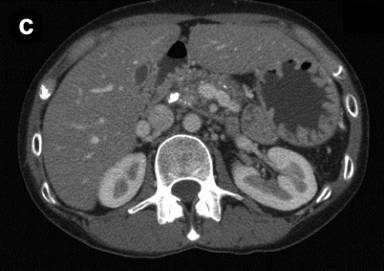

Figure 1. Abdominal enhanced CT in two patients with calcified chronic pancreatitis. a. b. Case #1. c. d. Case #2. |

In case #2, the patient was a 34-year-old woman who was diagnosed with alcoholic calcified chronic pancreatitis and a pancreatic pseudocyst six years ago. An infectious pancreatic pseudocyst was treated with pancreatic tail resection. Subsequently, she showed satisfactory improvement. However, the pain reappeared after she resumed drinking two years previously. Abdominal CT revealed a relatively large pancreatic stone in the main pancreatic duct in the pancreatic head (Figure 1c) as well as small diffuse stones in the pancreatic body (Figure 1d). She was started on an oral elemental diet at home.